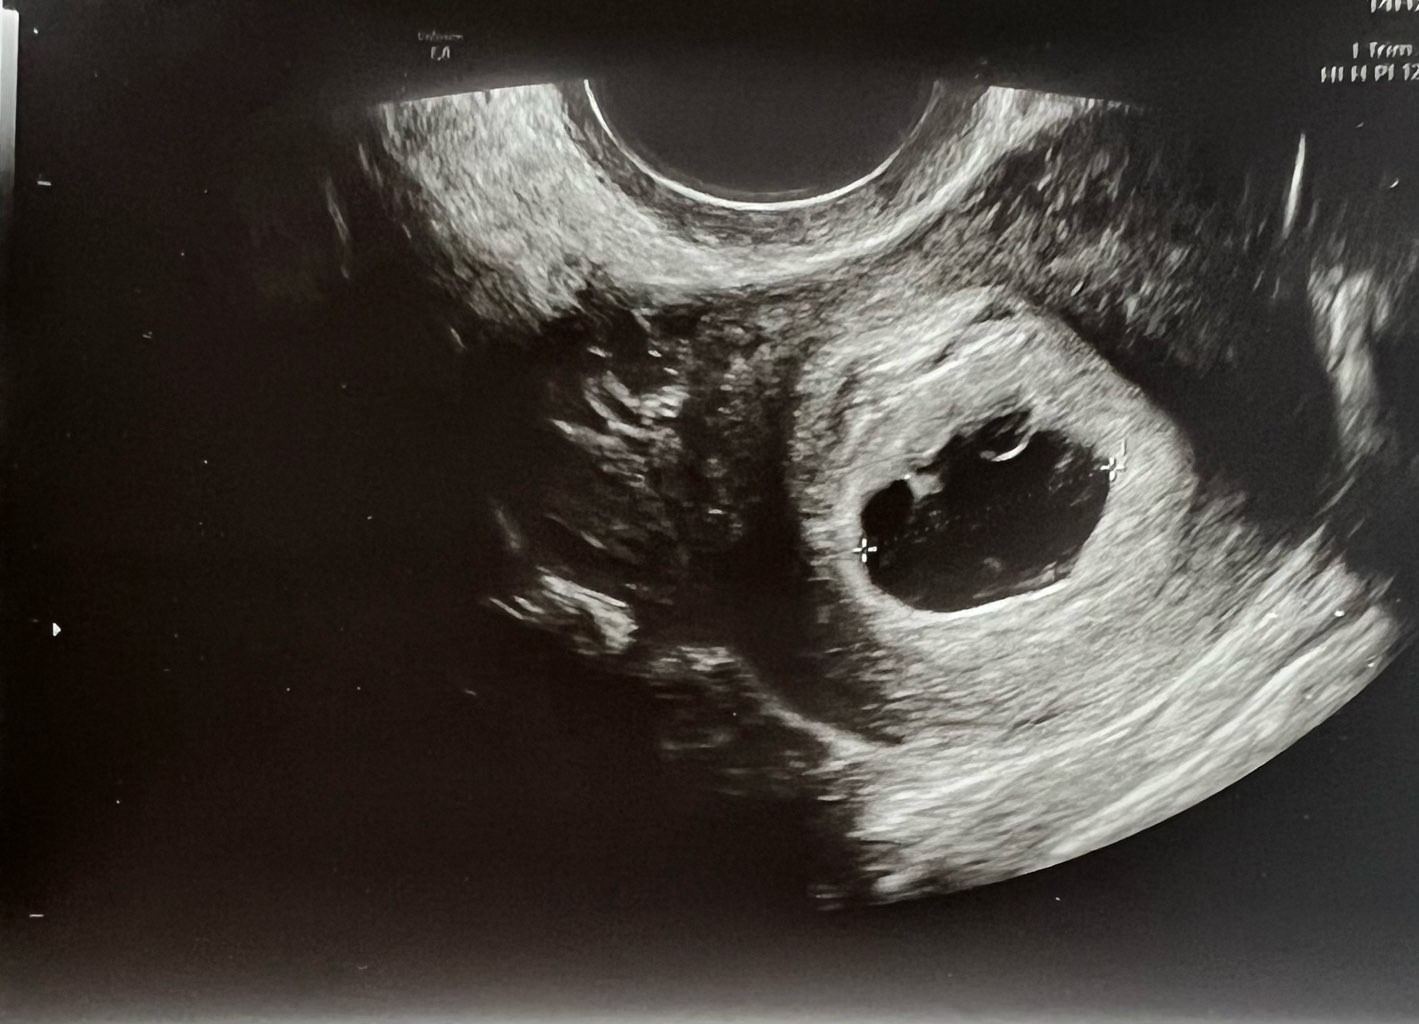

Czy któraś z Was miała podobny pęcherzyk?

Lekarz stwierdził tylko, ze nie wie co ma o tym myśleć… bo jest duży i nieregularny…

Mam krwiak 17mm, raz poleciała mi krew, ale serduszko zaczęło bić.

2 tyg temu pęcherzyk ciążowy był okrągły, a teraz jest taki dziwny

6t4d, CRL 0,67cm, biorę luteinę i neoparin